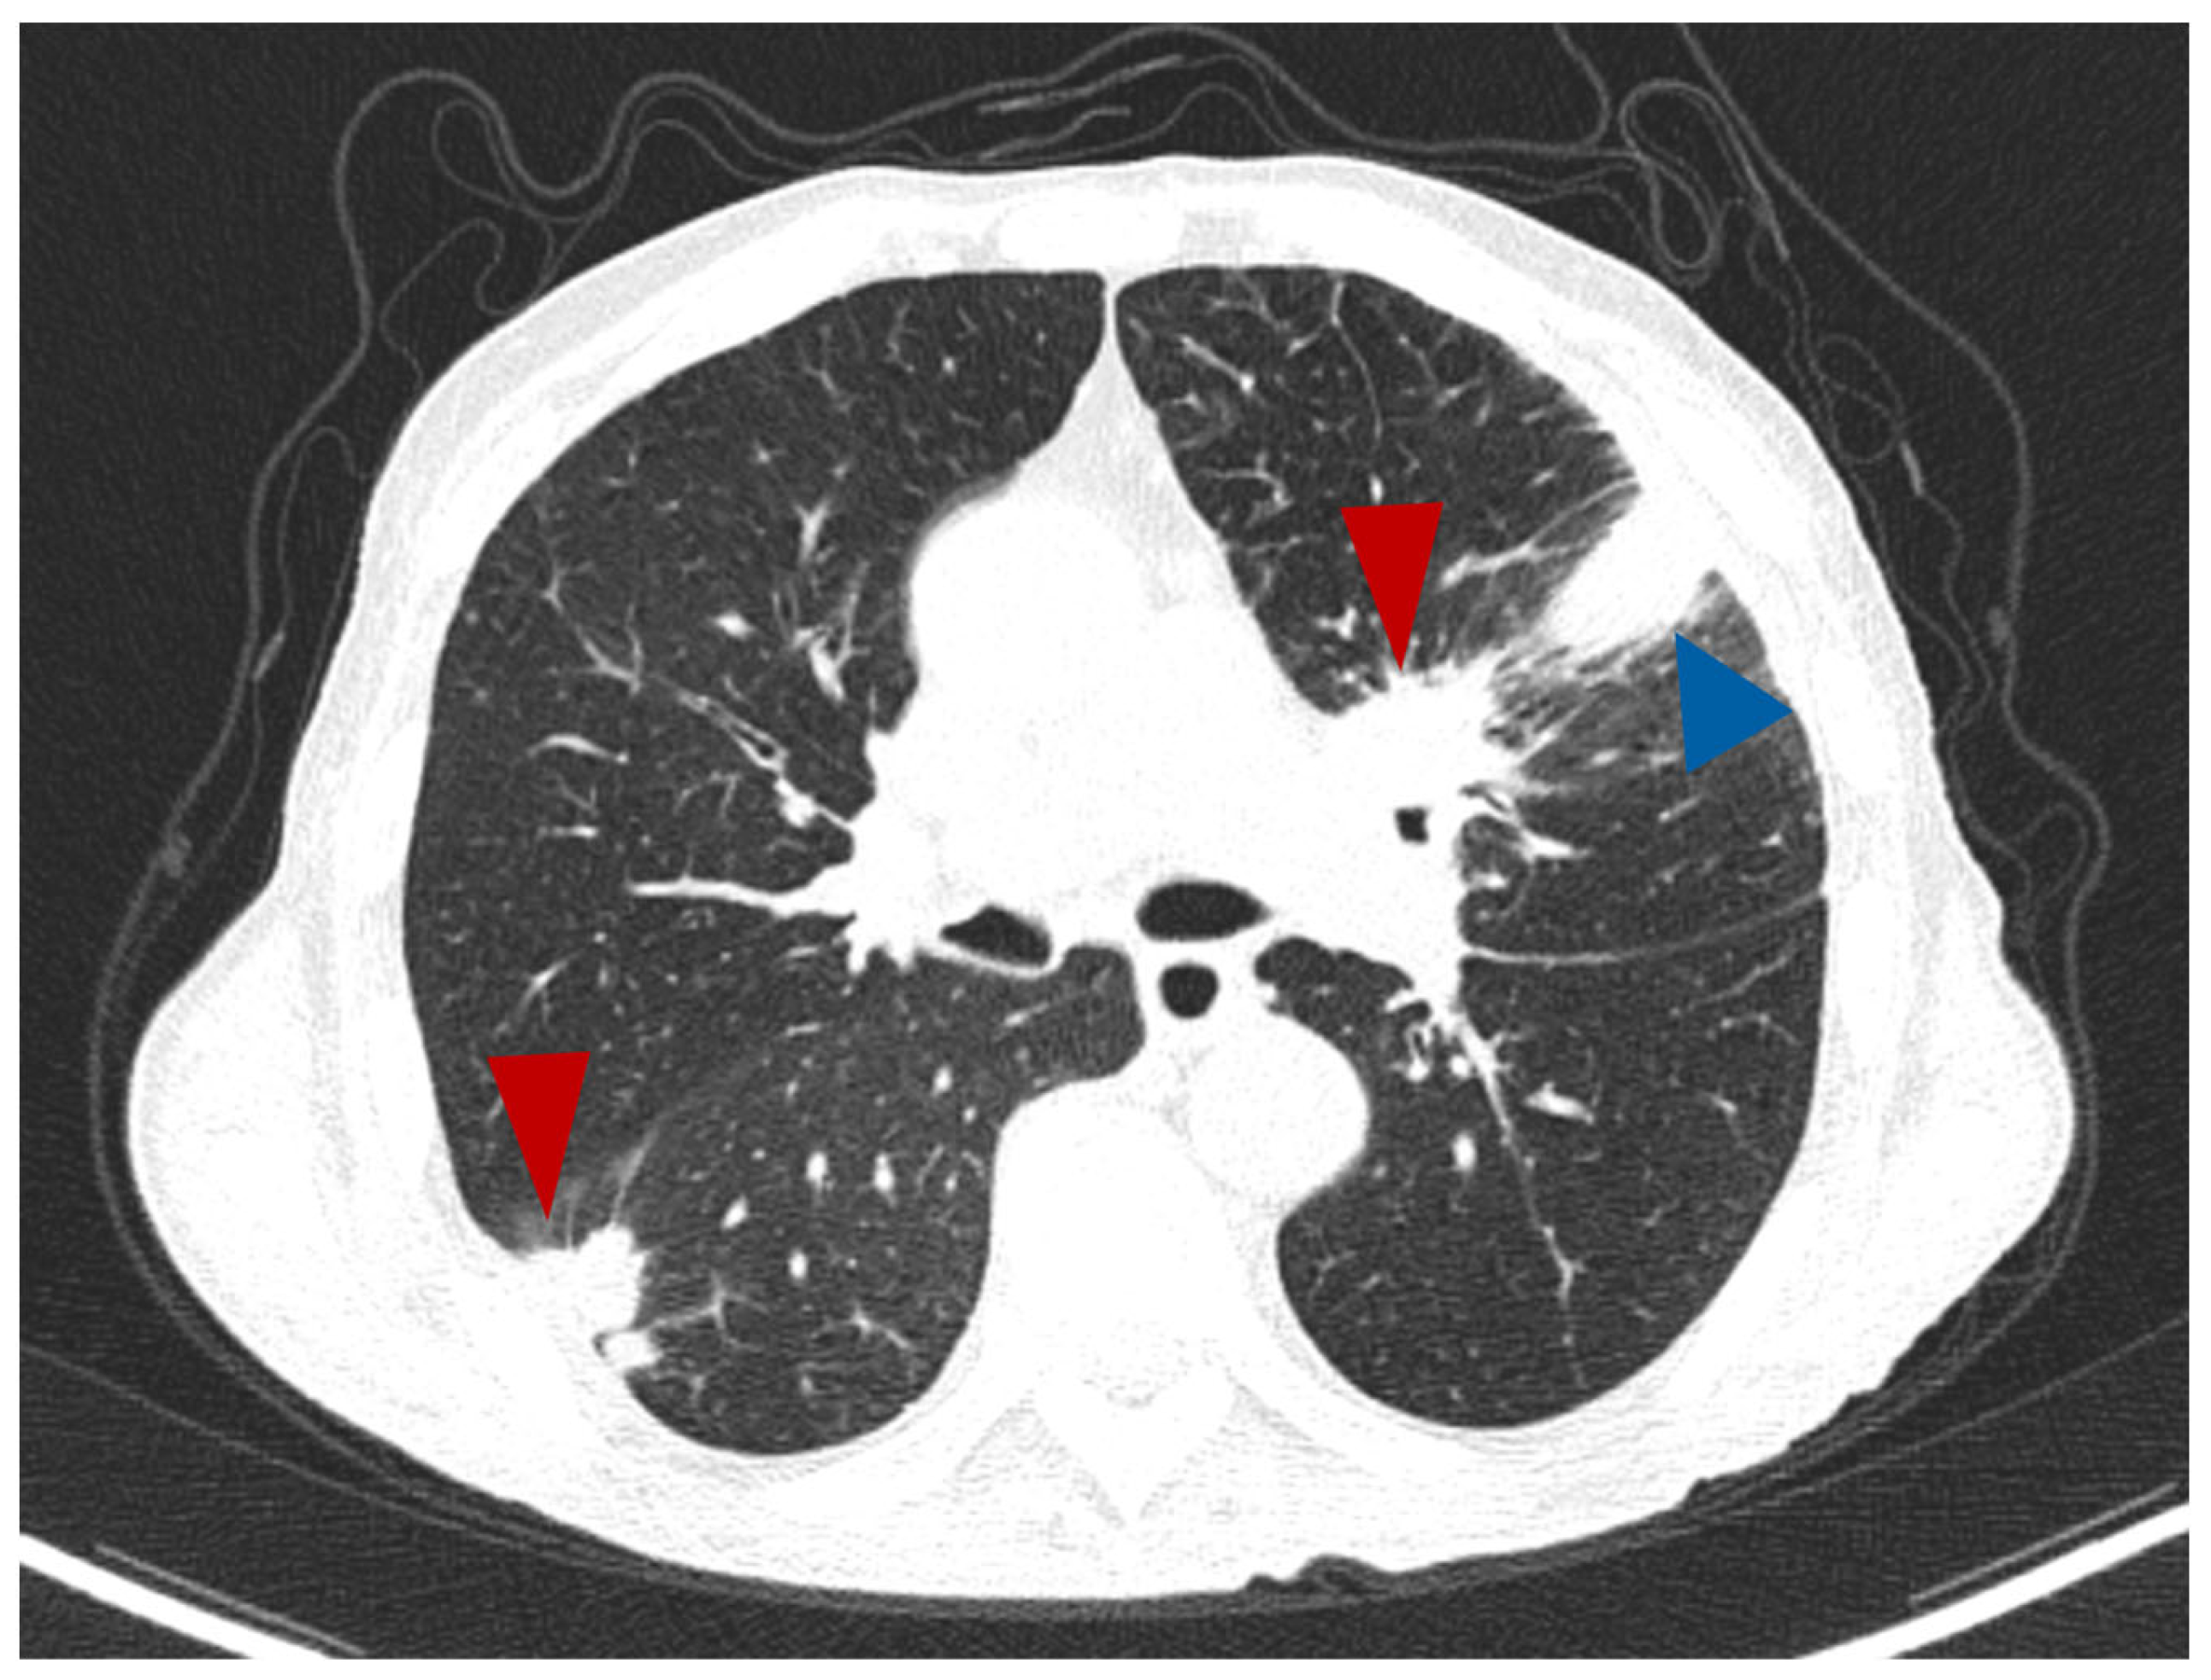

A single tumour was observed in almost all cases. There were only two cases with more than one tumoral mass, with CT features suggestive for a primary lesion in the adenocarcinoma group (7.7%), as exemplified in Figure 4, and two cases in the SQCC group (9%). All cases from the SCLC group showed a single primary tumour per patient.

Figure 4.

Axial CT lung window—a case of lung ADC with two spiculated masses (red arrowhead), one in the right lower lobe and the other one in upper left lobe, which in this second location combines a segmental atelectasis (blue arrowhead).